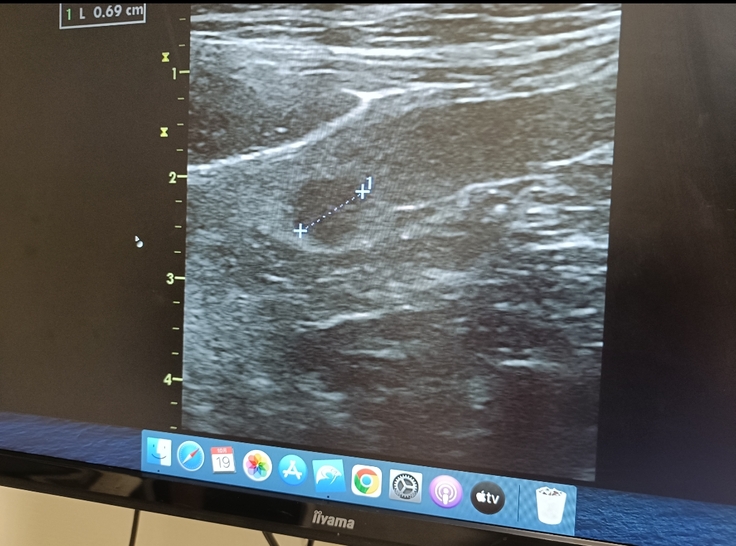

喉のしこりに関しては1cm以下で、このサイズだとほとんどの飼い主さんは気づかないらしく「よく見つけたね」と先生に声をかけて頂けました。